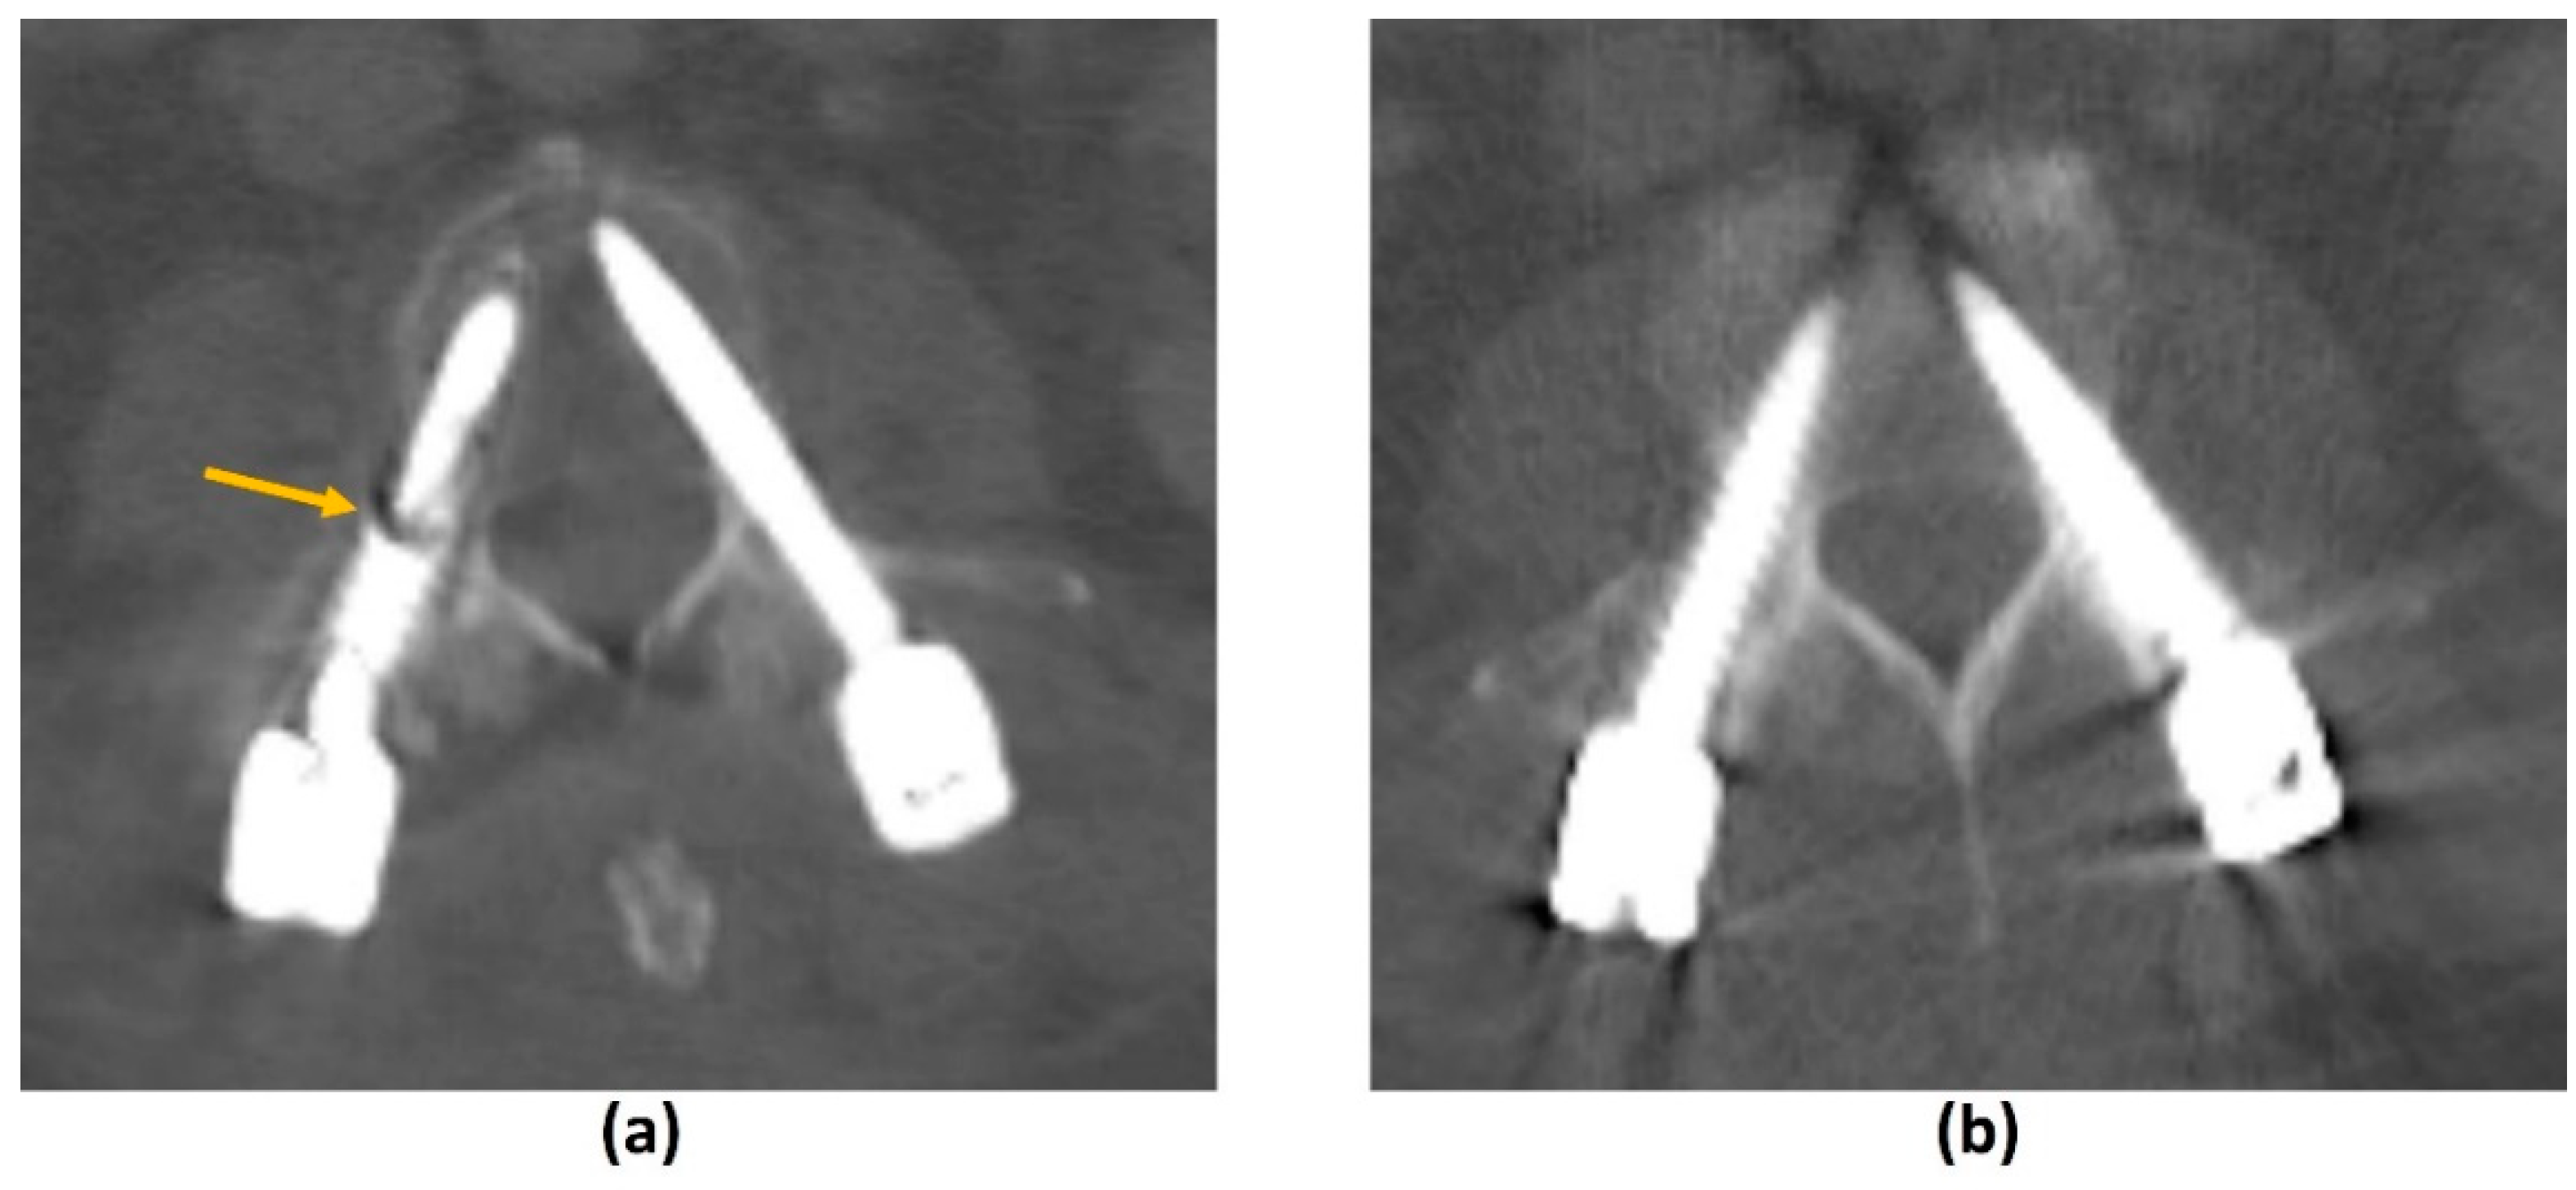

3.4.1. Challenges of CT: Metal-Related Artifacts

3.4.2. Photon-Counting CT